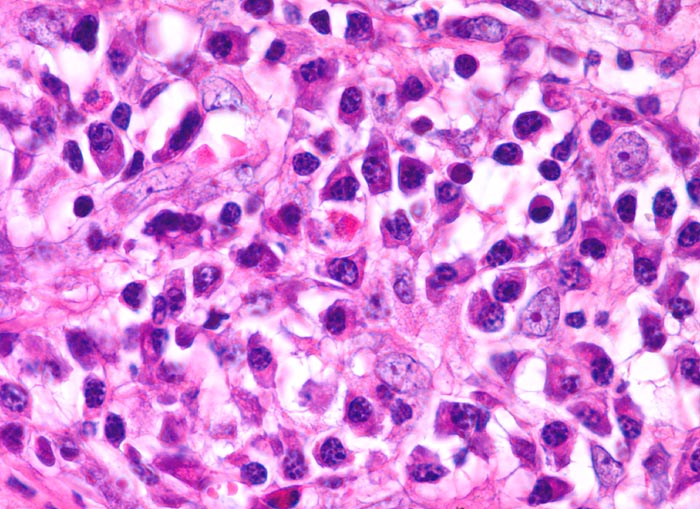

• Reed-Sternbergzelle mit spiegelbildlich angeordneten Kernen mit sehr grossen eosinophilen Nukleolen.

• Einkernige Hodgkinzelle mit prominentem Nukleolus umgeben von einem Retraktionsartefakt (Lakunarzelle).